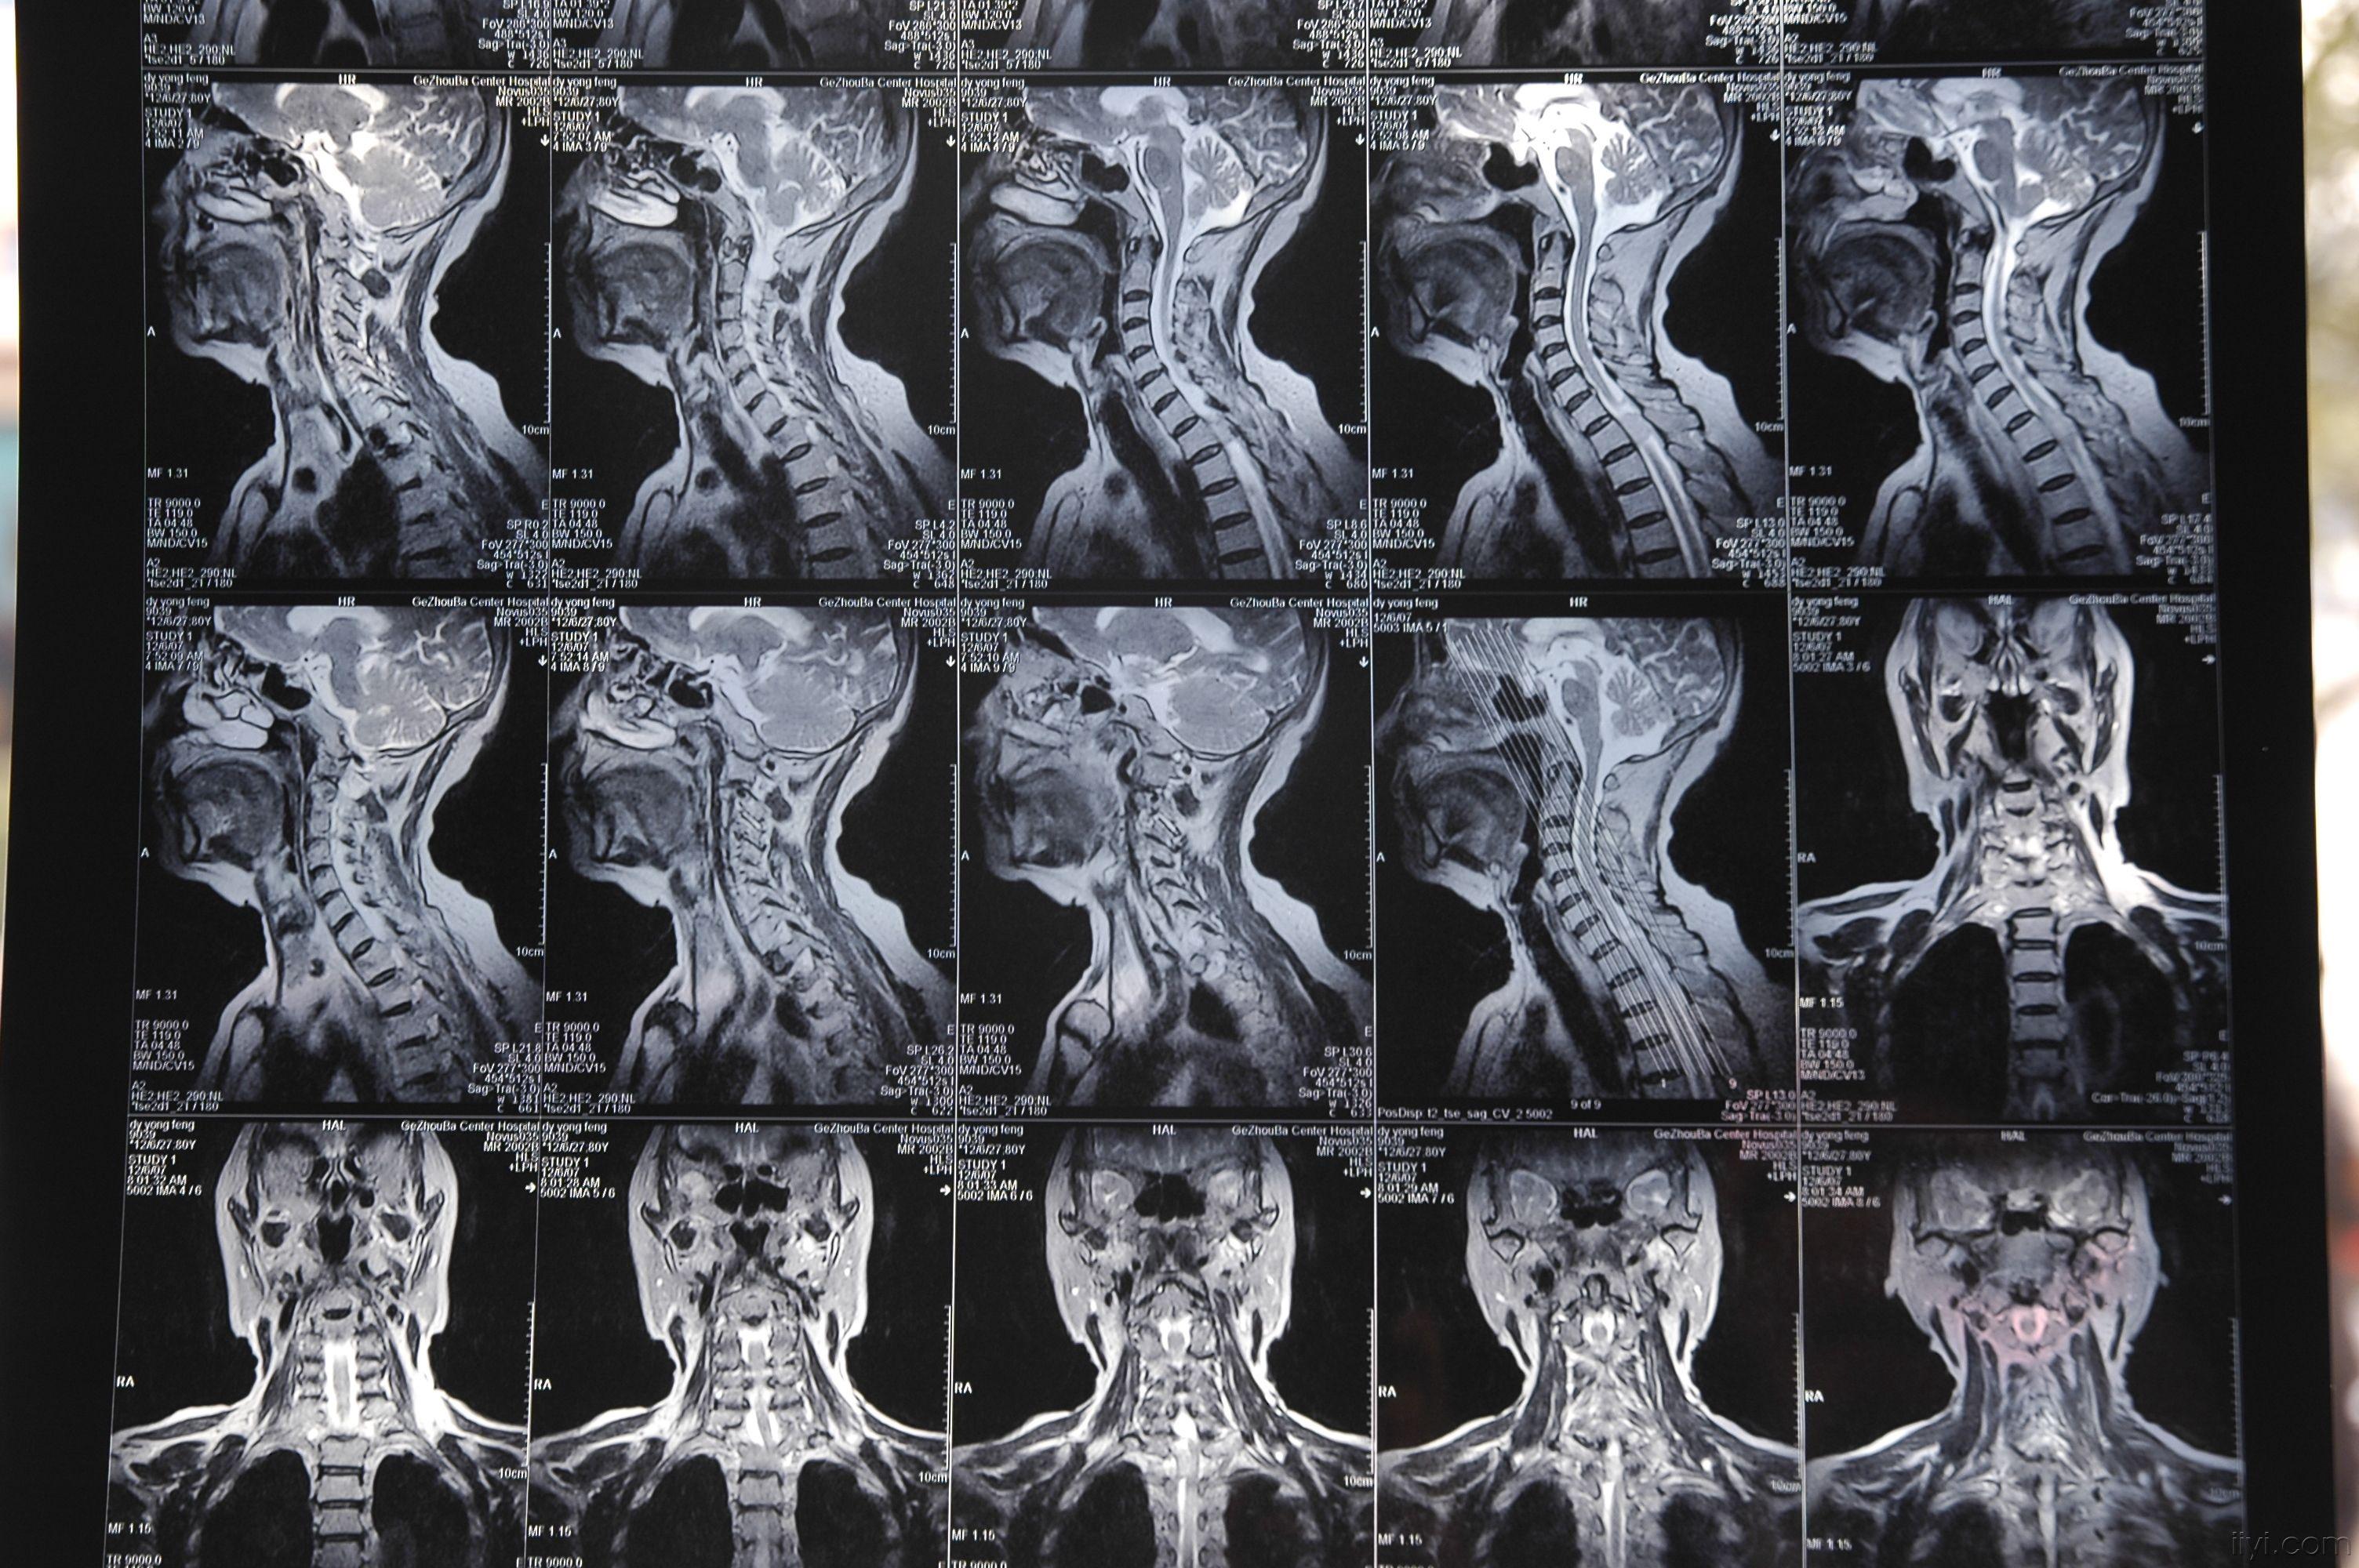

大家帮我看个片子

图片尺寸3008x2000